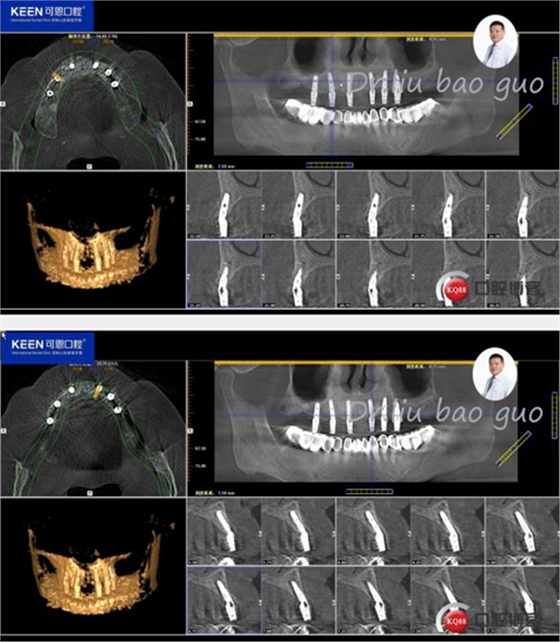

術(shù)后照片